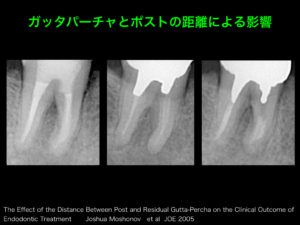

当院では根管治療のご依頼を頂いた際に根管充填後、原則として支台築造までを行わせていただいております。

通常(Pro root MTAなどのバイオセラミックで根管充填、パーフォレーションリペアと同時に根管充填を行う以外)は根管充填後、ラバーダム防湿下にて即時に直接法にて支台築造を行います。